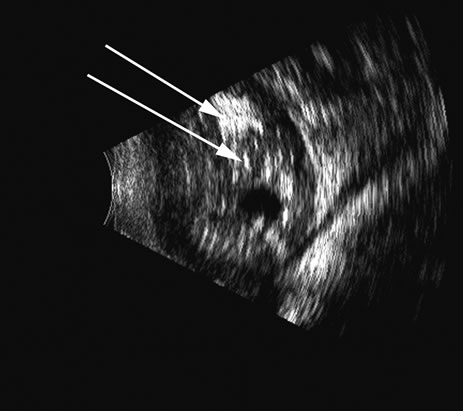

Fig. 4. A clinically well-placed posterior chamber intraocular lens nevertheless had patient complaints of photophobia and irritation due to a folded haptic (arrow).

Fig. 5. An anterior chamber intraocular lens has had the support haptics dislocate posterior to the iris plane and can be seen as typical foreign body echogenic reflections (arrows).